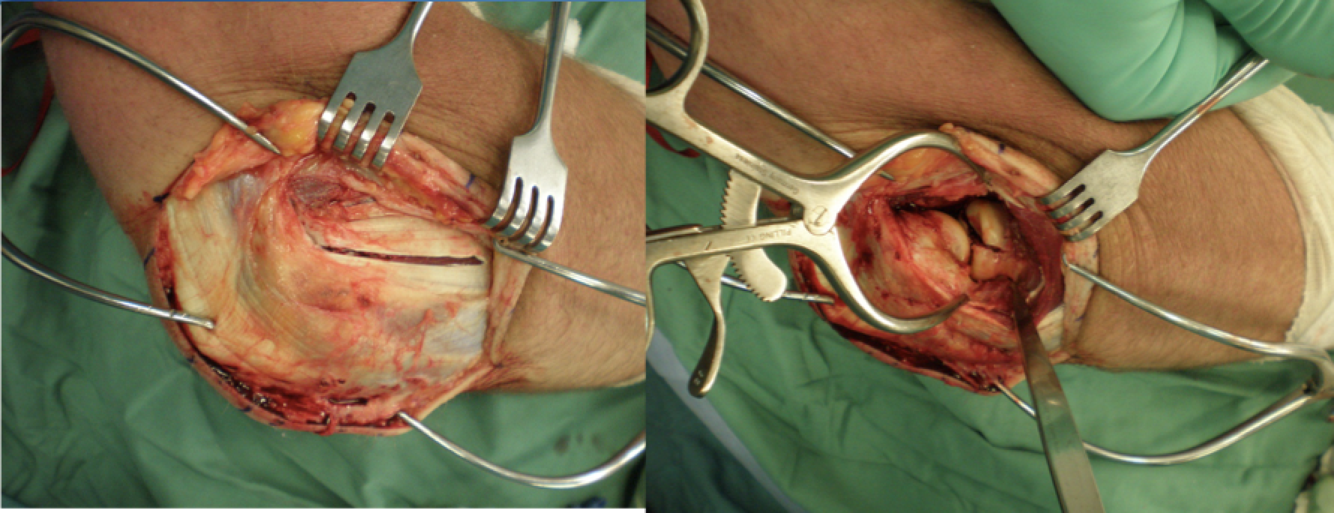

Olecranon Osteotomy

Interval: n/a

Approach: Apex distal osteotomy ~2cm distal to olecranon tip. Into “bare area” of sigmoid notch. Saw 1/2- 2/3 of the way in, then finish with osteotome to get interdigitation. Can predrill olecranon to give good reduction after. Can extend from a paratriciptal/triceps split.

Dangers: Articular surface distal humerus/ulna.

Triceps Reflecting Anconeus Pedicle (TRAP)

Interval: Kocher Anconeus (radial n.), ECU (PIN) distally, triceps peel proximally

Approach: Establish the Kocher interval, then proceed to release the ulnar insertion of anconeus, while maintaining its fascial connection to triceps. Can then elevate the triceps off the olecranon.

Dangers: Radial N. PIN, LUCL

* Thought to preserve innervation to Anconeus

Bryan-Morrey Triceps Reflecting

Interval:

- Proximally Triceps (radial n.) & lateral intramuscular septum.

- Distally- Kocher: anconeus (radial n) & ECU (PIN). keeping fascial connection between Anconeus and triceps.

Approach: Identify, expose and protect ulnar n. elevate triceps from intramuscular septum and off of olecranon. Distally the flap is based on the attachment of the anconeus. Keep attachement between triceps and anconeus.

Dangers: Ulnar N. Radial N. proximally and laterally. LUCL